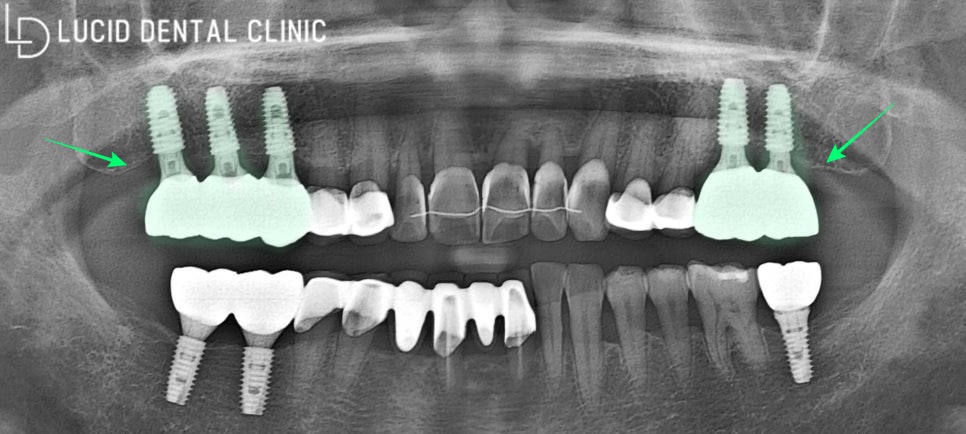

- 임플란트 수술 종료

서초동 치과 에선 지르코니아 재료를

이용하여 보철을 제작하고 있습니다.

보다 높은 심미성과 강도를

자랑하는 재료이기 때문이죠.

사진과 같이 무사히 체결한 다음,

교합 조정과 연마 작업을 시행하며

별다른 문제없이 마칠 수 있었습니다.

환자께 조금 더 오랜 수명과

안정된 구강 환경을 유지하도록

계속해서 정기 검진을 받으라고

여러 번 당부해 드리고 마쳤어요 :)